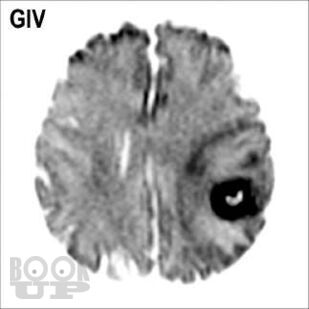

Книга «Опухоли мозга. КТ- и МРТ-диагностика» посвящена диагностике опухолевого поражения центральной нервной системы. При этом широко раскрыты особенности морфологической структуры каждой конкретной опухоли головного мозга. Структура изложения материала основана на классификации опухолей головного мозга по рекомендациям ВОЗ. Представленные опухоли в заголовке содержат шифр МКБ/О из 10-го пересмотра. Под каждым диагностическим изображением имеется подпись с обозначением его характеристик: метод исследования (КТ, МРТ, рентген, ПЭТ и др.), название ширины окна для КТ или импульсной последовательности на МРТ, а также ориентация среза в пространстве (аксиальный, сагиттальный или корональный). Данная особенность позволяет улучшить восприятие изображений, а также избежать путаницы при сопоставлении разных импульсных последовательностей и окон на МРТ и КТ.